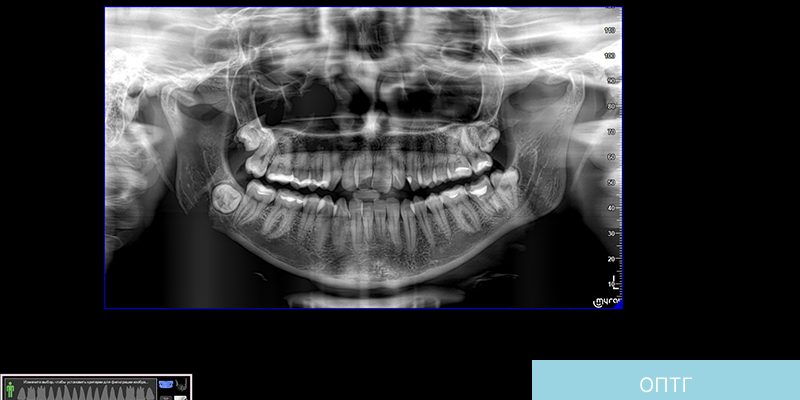

ИИ в стоматологии: Как нейросети читают ортопантомограммы и меняют наш подход к лечению Мы живем в эпоху стремительных перемен‚ когда искусственный